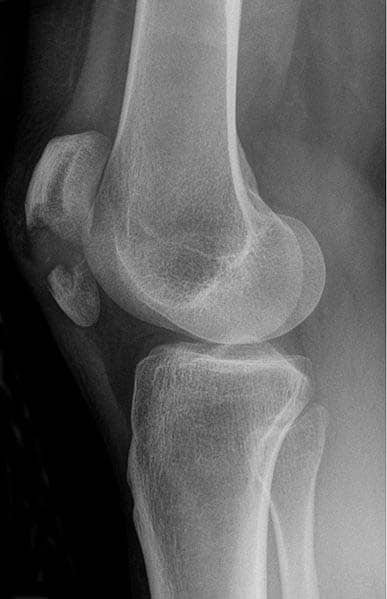

The patella (kneecap) is located at the front of the knee joint, within the patellofemoral groove of the femur. Its superior aspect is attached to the quadriceps tendon and inferior aspect to the patellar ligament. It is classified as a sesamoid type bone due to its position within the quadriceps tendon, and is the largest sesamoid bone in the body. In this article we will look at the anatomy of the patella – its surface features, functions and clinical relevance. By TeachMeSeries Ltd (2025) Fig 1The position of the patella within the lower limb Pro Feature - 3D Model You've Discovered a Pro Feature Access our 3D Model Library Explore, cut, dissect, annotate and manipulate our 3D models to visualise anatomy in a dynamic, interactive way. Learn More Bony Landmarks The patella has a triangular shape, with anterior and posterior surfaces. The apex of the patella is situated inferiorly and is connected to the tibial tuberosity by the patellar ligament. The base forms the superior aspect of the bone and provides the attachment area for the quadriceps tendon. The posterior surface of the patella articulates with the femur, and is marked by two facets: Medial facet – articulates with the medial condyle of the femur. Lateral facet – articulates with the lateral condyle of the femur. By TeachMeSeries Ltd (2025) Fig 2Anterior and posterior surfaces of the patella. Functions The patella has two main functions: Leg extension – Enhances the leverage that the quadriceps tendon can exert on the femur, increasing the efficiency of the muscle. Protection – Protects the anterior aspect of the knee joint from physical trauma. Clinical Relevance Injury to the Patella Patellar Dislocation In a patellar dislocation, the patella bone is displaced out of the patellofemoral groove. It accounts for around 3% of knee injuries. Most dislocations occur laterally and are caused by high force impact on the patella or forceful sudden twisting of the knee. These mechanisms of injury make patellar dislocation more common in individuals participating in sports such as: football, rugby and ice hockey. Patellar Fracture Patellar fractures usually result from direct trauma to the bone, or sudden contraction of the quadriceps muscle. They are more common in males, and in the 20-50 age range. If the patella fractures into fragments, they will usually separate; the proximal fragment displaced superiorly by the quadriceps tendon and the distal fragment pulled inferiorly by the patellar ligament. By Hellerhoff (Own work) [CC BY-SA 3.0], via Wikimedia Commons Fig 3Radiograph of patella fracture. Note the displacement of the proximal and distal fragments. Do you think you’re ready? Take the quiz below Pro Feature - Quiz The Patella Question 1 of 3 Submitting... Skip Next Rate question: You scored 0% Skipped: 0/3 1800 More Questions Available Upgrade to TeachMeAnatomy Pro Challenge yourself with over 1800 multiple-choice questions to reinforce learning Learn More Rate This Article